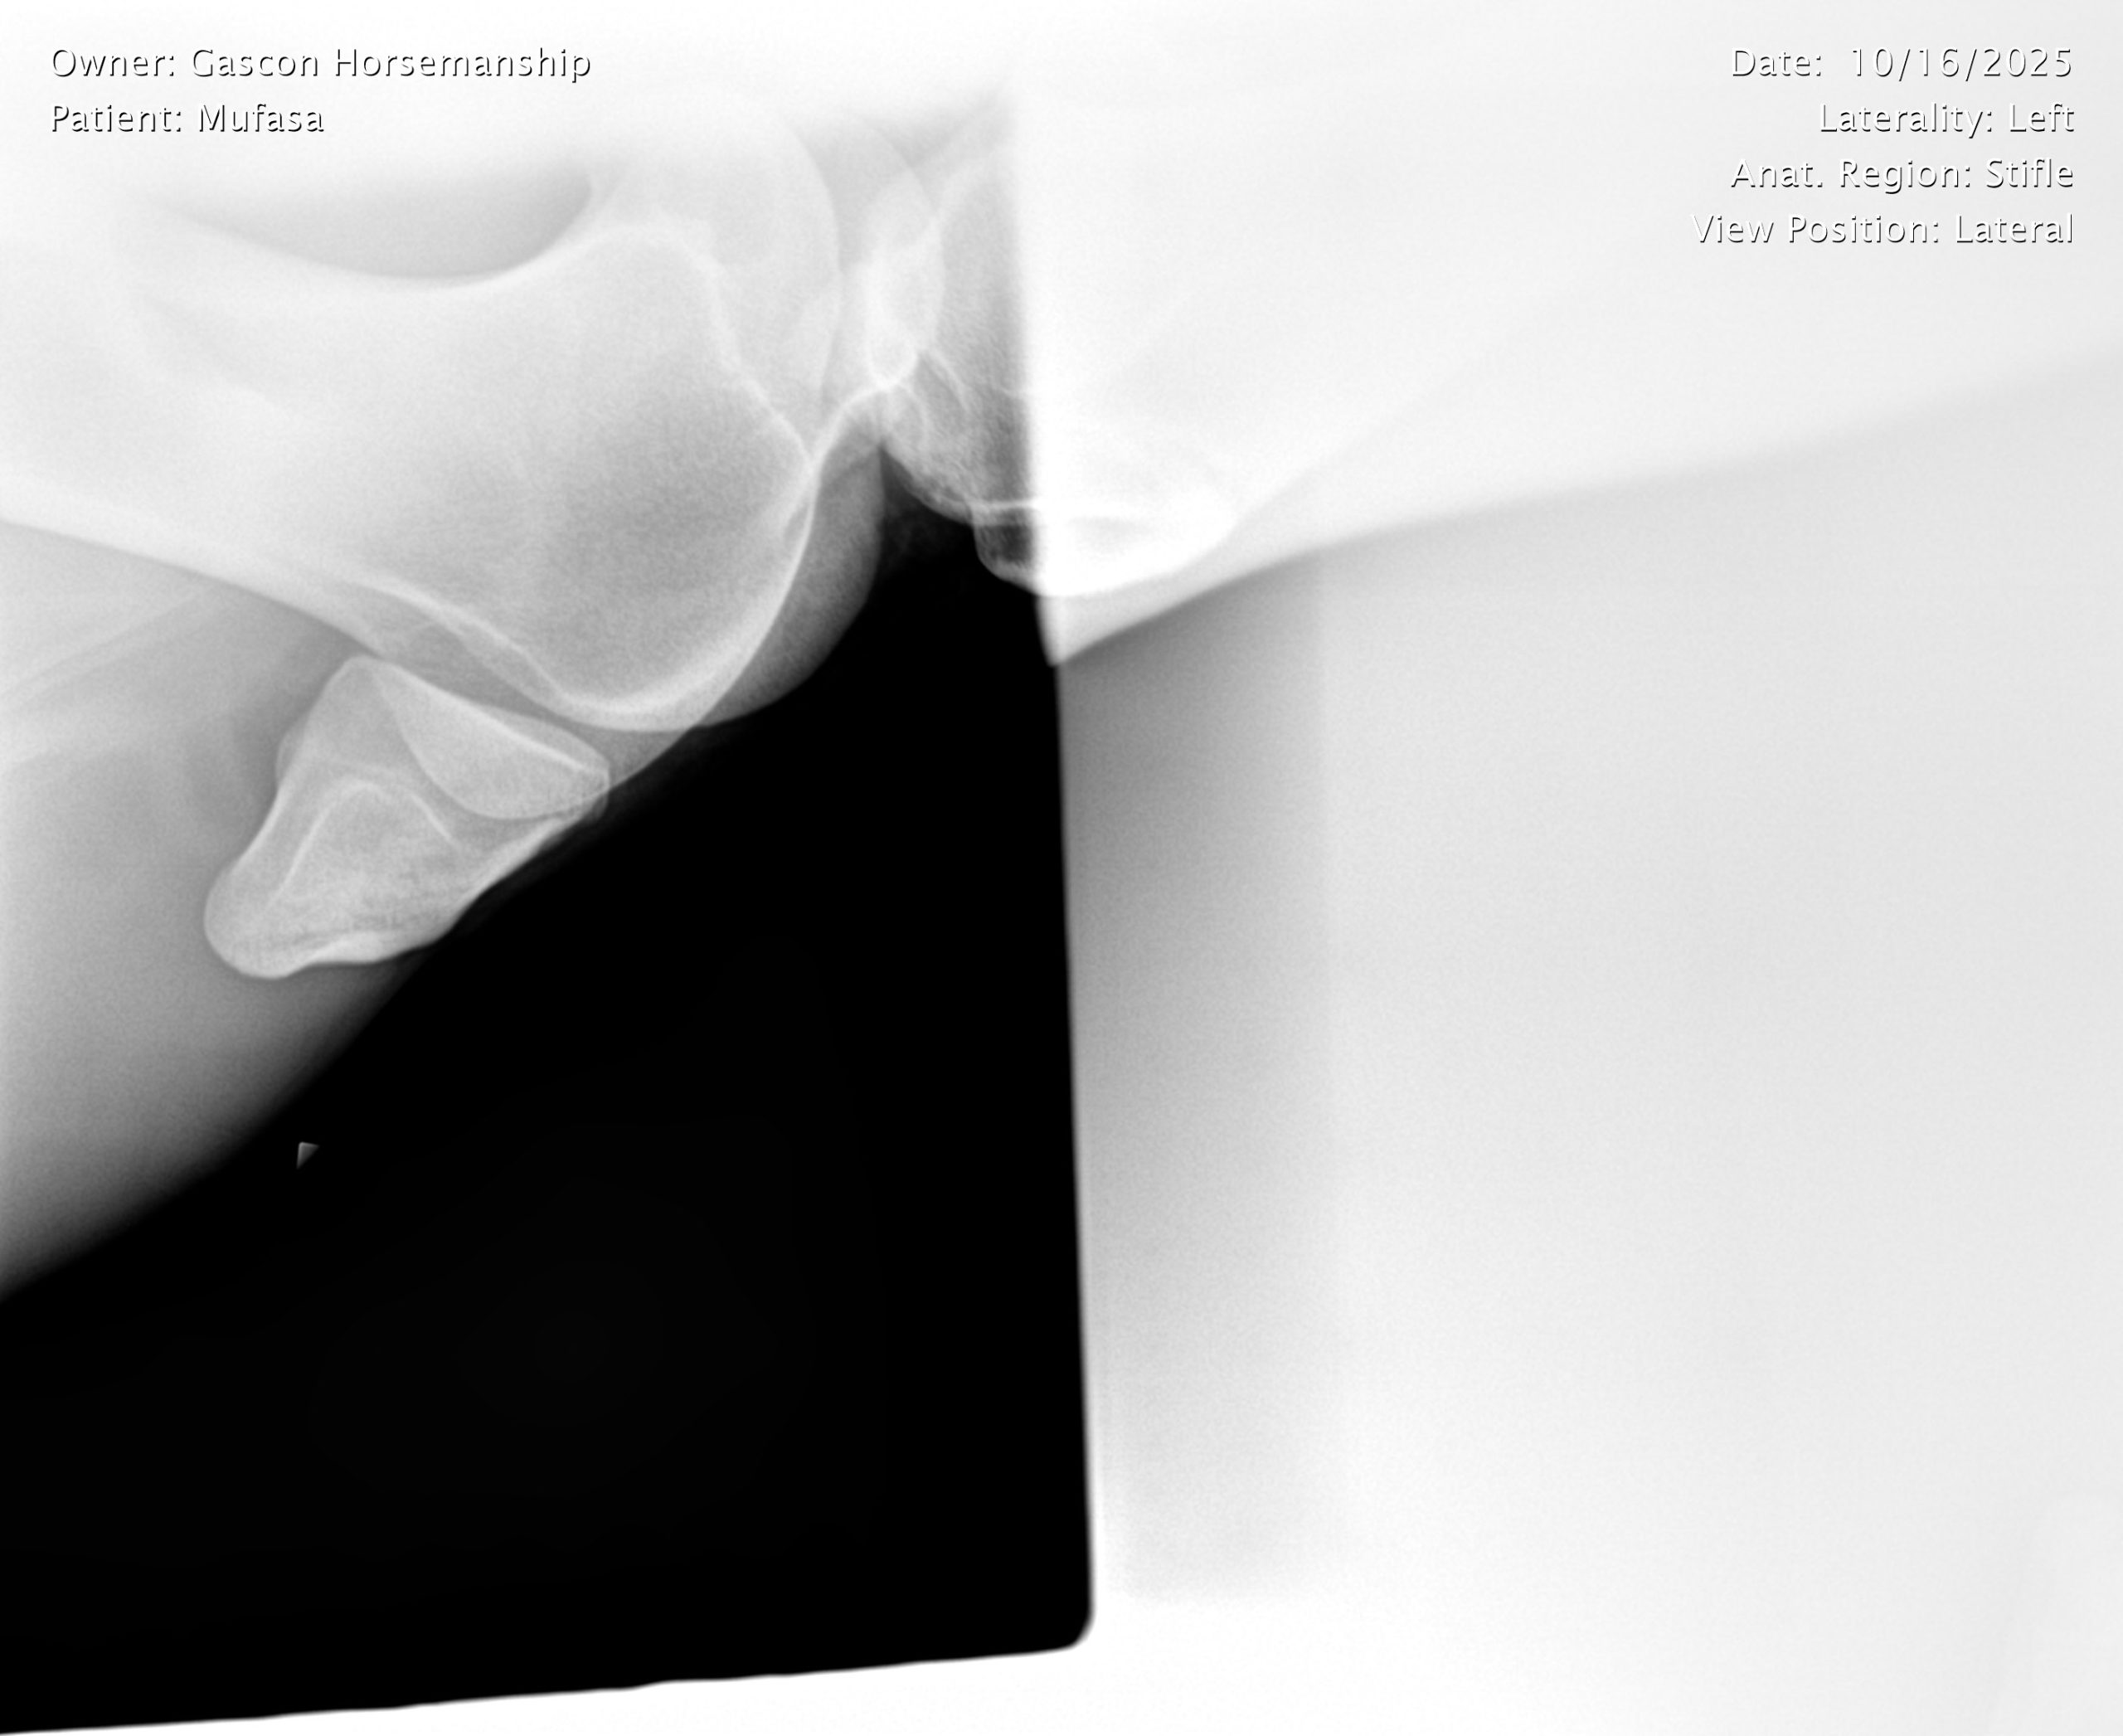

He already has a full pre-purchase exam on file, complete with 25 X-rays included in his album.